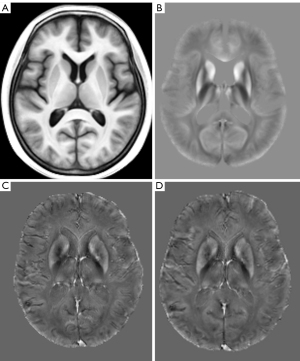

The QSM post-processing steps and the whole-brain analysis were conducted using an optimized pipeline in QSMexplorer (https://gitlab.com/acostaj/QSMexplorer) (27). Briefly, a study-specific structural template was generated from the bias-corrected 3D-FSPGR images of all participants, following the “antsMultivariateTemplateConstruction2” routine with six full runs in Advanced Normalization Tools (ANTs; http://stnava.githib.io/ANTs); simultaneously, the individual T1-weighted structural images were spatially normalized to the template using the “SyN” approach in ANTs. Then, the first-echo magnitude images were corrected for bias field and rigidly coregistered to their corresponding T1-weighted structural images. The QSM images were subsequently warped to the study-specific T1-weighted template for spatial normalization through a method combining the above-mentioned transformations and third-order b-spline interpolation in ANTs. We also created a study-specific QSM template by averaging the normalized QSM images across the participants (Figure 1). In addition, the 3D-FSPGR images were segmented to obtain probabilistic maps of the gray matter for further analysis using the SPM12 software (http://www.fil.ion.ucl.ac.uk/spm/software/spm12).